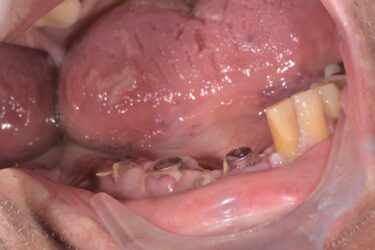

Hi I have an implant bridge case to restore. Pt is in his 80s. I have just been restoring single units before this and would love some help/advice about how to proceed. The initial idea was just to scan, which I’m comfortable doing. But I have learned that the scanner may not be so accurate for larger cases like this. I will order a special tray first of all.

Some questions that come to mind

1) do people scan cases like this with good success

2) how would u take a bite registration on the right hand side

3) what happens if the pt can’t open up wide enough for open tray technique

4) after impression or scanning do u go straight to issue or is there a step worth taking in between